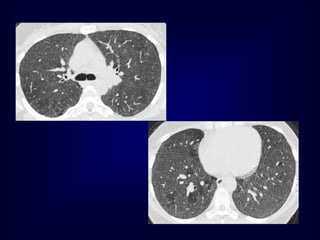

Mosiac pattern

Where is the pathology ???????

in the areas with increased density

meaning there is ground glass

in the areas with decreased density

meaning there is air trapping

Airway Disease

what you see……

In inspiration

sharply demarcated areas of seemingly increased

density (normal) and decreased density

demarcation by interlobular septa

In expiration

„black‟ areas remain in volume and density

„white‟ areas decrease in volume and increase in

density

INCREASE IN CONTRAST

DIFFERENCES

AIRTRAPPING